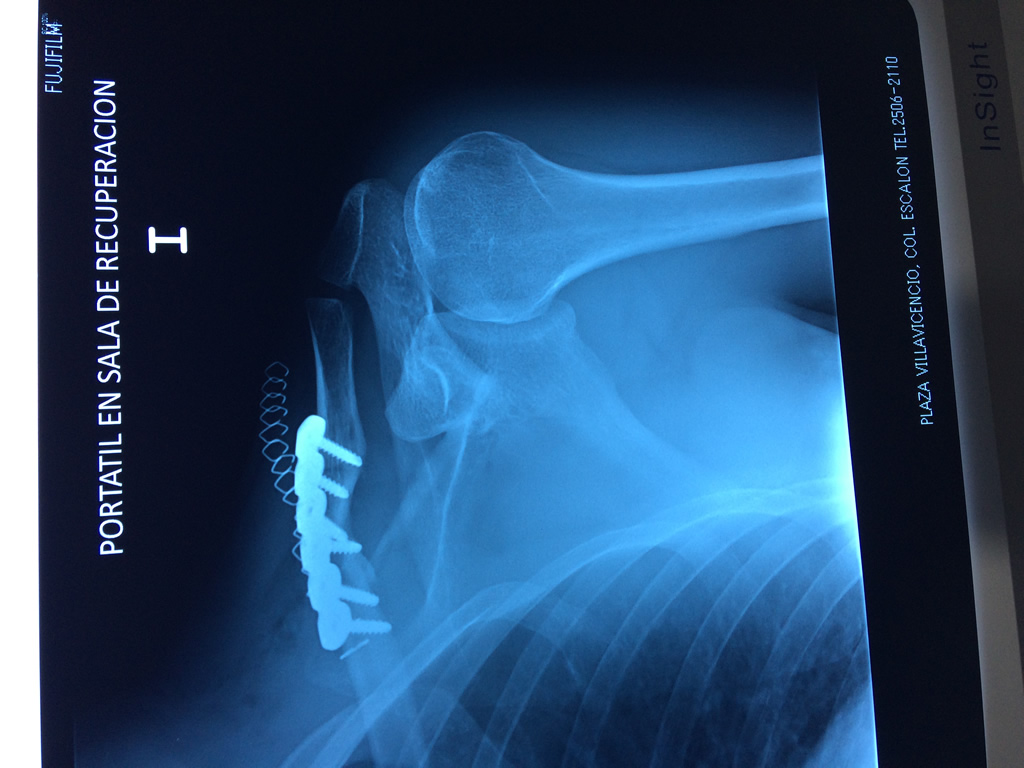

Se considera el único medio de unión entre el miembro superior y el tórax. A pesar de su aspecto, similar al de un hueso largo, posee una estructura semejante a la de un hueso plano, ya que carece de epífisis y de diáfisis, lo que la harían entrar dentro de la clasificación de hueso largo. Carece de un canal medular propiamente dicho.